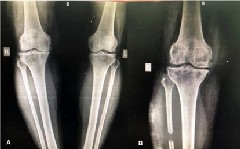

Проксимальная корригирующая остеотомия малоберцовой кости ослабляет боковую поддержку малоберцовой кости и приводит к коррекции варусной деформации, которая впоследствии может смещать направление нагрузки от медиального отдела в сторону латерального отдела, что приводит к уменьшению боли и удовлетворительному функциональному восстановлению.

Вкратце, боковой разрез от 3 до 5 см делается в проксимальной трети малоберцовой кости. Затем фасцию рассекают, мышцы отодвигаются, малоберцовую кость обнажают. Проводится резекция малоберцовой кости длиной 2 см на 6-10 см ниже головки малоберцовой кости с помощью осциллирующей пилы. После резекции концы малоберцовой кости замазывают костным воском. Мышцы, фасции и кожа ушиваются послойно.